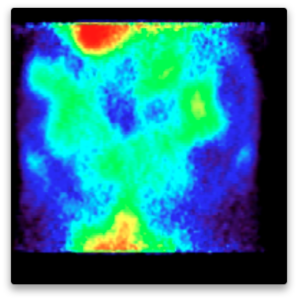

Just as it is possible to label a drug to find out whether it crosses the blood-brain barrier and then to measure the uptake and washout kinetics into the brain, it is also possible to use the labeled drug to measure uptake elsewhere. In this case the question is whether a drug reaches a fetus across the placental barrier. Reasons can include a desire to treat the fetus, or a desire to choose a drug partly on the basis of its exclusion from the fetus to minimize fetal toxicity and teratogenicity. These examples show selected images obtained from a study of live pregnant rats injected with I-124 labeled drug at 8, 11, 12 and 20 days of gestation. Injections were done at varying times, images shown are primarily of the abdomen only.

The “string of pearls” image of the fetuses is visible in the images. The rats had at least nine fetuses. From the whole-animal image at 8 days it is clear that this molecule did NOT accumulate well in the uterus or fetuses. The vast majority of administered dose was excreted. This can be a good result, of course. Further, uptake in this case appears to be in the placental areas and not in the uterine wall or contained within the fetuses.